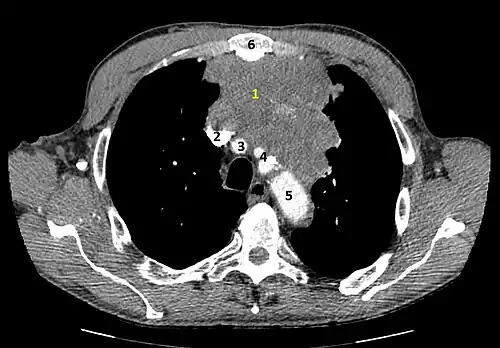

Scanner injecté, en fenêtre médiastinale, montrant un carcinome thymique envahissant les structures médiastinales :

1 : tumeur hétérogène, aux contours irréguliers, présentant des plages hémorragiques ;

2 : veine cave supérieure ;

3 : tronc artériel brachiocéphalique ;

4 : artères sous-clavière gauche et carotide commune gauche ;

5 : crosse de l'aorte ;

6 : sternum.- Scanner en fenêtre parenchymateuse, montrant un carcinome thymique envahissant les poumons (avec des lésions d'emphysème) au contact des deux poumons (1 : poumon droit ; 2 : poumon gauche) ;